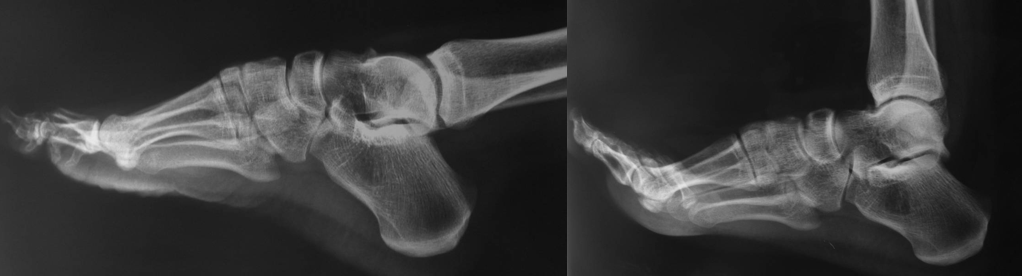

外踝骨折

王岩  男  24岁

软组织撞击

术后复查